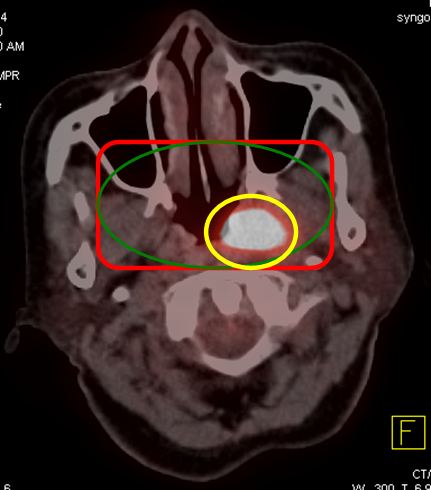

Mô phỏng tốt nhất trên PET/CT với hệ thống laser định vị 3 chiều. Vì PET/CT ghi hình dựa trên sự tập trung cao thuốc phóng xạ FDG vào các tế bào ung thư, cho hình ảnh chuyển hóa của khối u, sớm, chính xác hơn hình ảnh giải phẫu của CT đơn thuần (hình 1), xác định được mức độ xâm lấn của u cũng như phát hiện những di căn hạch kể cả với kích thước nhỏ ở mức độ phân tử, mức độ tế bào từ đó cho phép xác định thể tích xạ trị cũng như việc lập kế hoạch xạ trị được triệt để nhất (hình 2). Khi chụp mô phỏng: bệnh nhân trong tư thế nằm ngửa, cổ ưỡn sao cho đường thẳng giữa cằm - xương chũm vuông góc với mặt bàn; đầu bệnh nhân được giữ cố định bằng mặt nạ, tổng hợp từ loại chất dẻo đặc biệt.

Hình ảnh CT mô phỏng khó xác định được vị trí khối u

Hình ảnh PET/CT mô phỏng thấy rõ khối u vòm

Hình 1: Hình CT và PET/CT mô phỏng ung thư vòm.